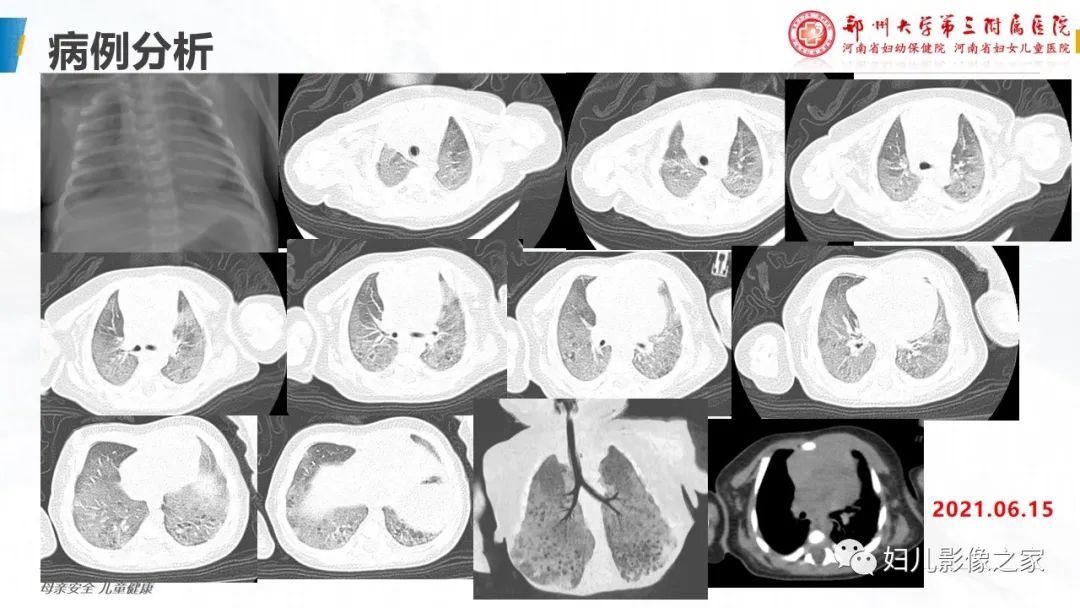

【PPT】肺泡蛋白沉积症的影像诊断-7